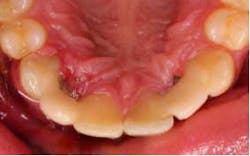

Three days before he left, the patient presented for treatment, the No. 7 implant had been removed, and the site had been grafted, along with No. 10 implant being submerged. A modified lingual veneer preparation was made on the adjacent teeth. The lingual prep served two purposes, the first to increase surface area for bonding and the second to increase the connector cross-sectional area. The ideal cross-sectional area is 16 mm² (*).

The preps were scanned, along with a bite registration, opposing dentition, and the diagnostic wax-up for cloning. The restorations were designed and milled from monolithic e.max HT blocks. The restorations were stained, glazed, and crystalized to final shade and luster.

The restorations were etched with phosphoric acid, cleaned with Ivoclean (*), and bonded with universal bond (*). The preparations were isolated (isolation was very difficult in the area of No. 7 due to surgery the day before), etched, bonded, and the restorations were cemented. Special attention was paid to the occlusion on the FPDs, and all occlusal contact was removed from the connector area. Also, all anterior guidance was removed from the FPDs. The opposing dentition was reshaped to gain as ideal of a contact on the restorations as possible. The patient returned one prior to his leaving to verify his occlusion and post-treatment photographs. At this time, the patient was instructed about hygiene for the restoration and how to carefully function with the restorations. He seemed to be pleased with the functionality and esthetics of the restorations.